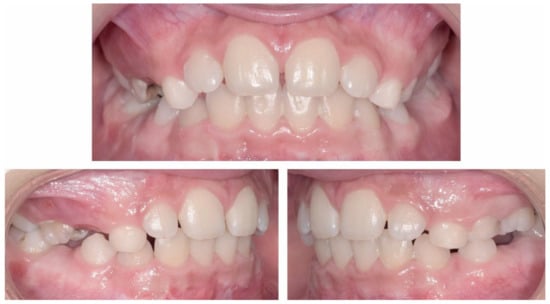

2.2.1. Initial Examination